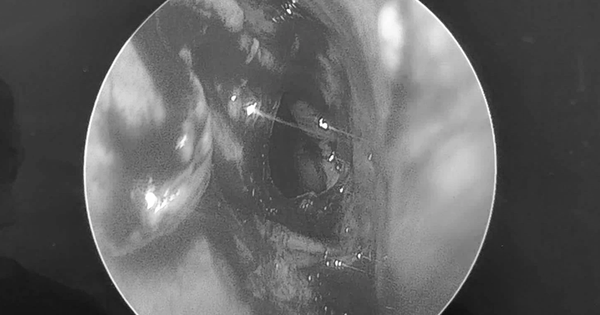

Bé trai đau vùng mắt dữ dội, bác sĩ sốc khi phát hiện dị vật "tàng hình"